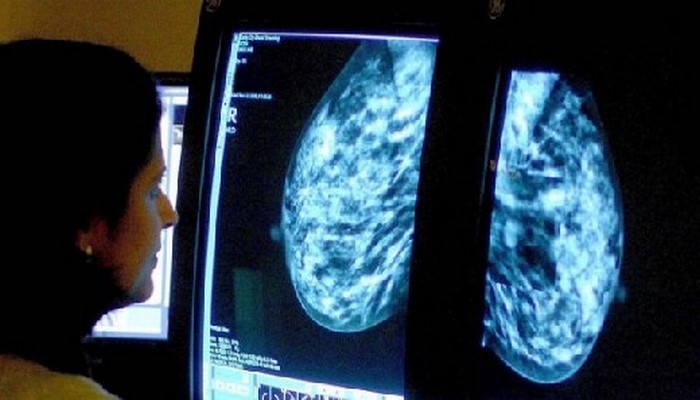

Обследование груди среди женщин в возрасте 40-49 лет спасает до 400 жизней ежегодно - исследование

Маммографическое обследование женщин в возрасте 40-49 лет, возможно, ежегодно спасает до 400 жизней, пришли к выводу ученые Лондонского университета королевы Марии.

В работе, которая была опубликована на страницах журнала Lancet Oncology, медики пришли к выводу, что обследование женщин в возрасте от 40 до 49 лет, сокращает количество летальных исходов от рака на четверть за первые 10 лет.